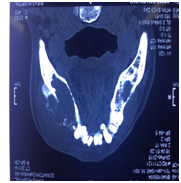

A 60 years old gentleman was referred to us in February 2015 with acute retention of urine. He was admitted to another hospital 5 days ago with the same problem he was treated with catheterization and failed trial without catheter after 3 days with alpha- blockers. Clinically he was cachectic and had a large, hard and non-tender swelling over his left lower jaw as shown in Figure 1 & Figure 2. There were no palpable cervical lymph nodes. Abdominal and Neurological examinations were unremarkable. Digital rectal examination revealed an enlarged T4 prostate cancer. Prostate Specific Antigen (PSA) was 100ng/ml. CT of Mandible showed a large destructive lytic lesion mass over the body of mandible reaching both buccal and lingual cortices and less pronounced lucency within the mandibular body with breech of buccal surface (Figure 3). CT chest showed sclerotic metastases throughout bony cavity with multiple pulmonary metastases (Figure 4). CT abdomen showed a markedly enlarged prostate gland (Figure 5) with secondary hypertrophy of the bladder wall, bilateral iliac lymphadenopathy measuring up to 3 cm and diffuses sclerotic metastases throughout the bony skeleton. Other solid organs are unremarkable.

Figure 3 CT of Mandible showing Buccal surface.